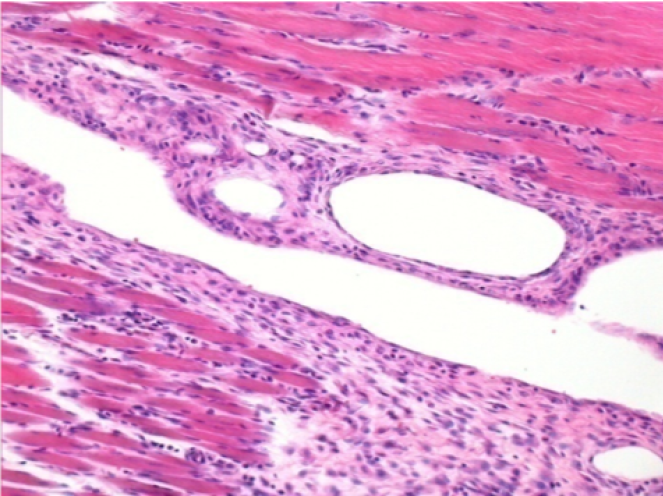

1 month after Endopeel Injection

1 month after Endopeel Injection 0.1ml in the right pretibial muscle.

What is seen in black on the pictures is not a necrosis like could imagine some scientifics !

In fact, 4 conclusions have to be taken in consideration

- an artefact of coloration

- an absence of necrosis

- an apoptosis

- a bioregenerative process

L : Control-100xD30

R:100xD30

R :400xD30